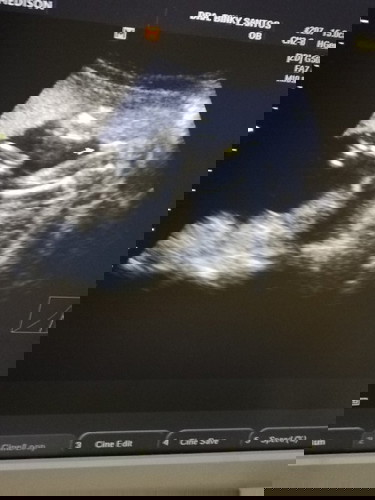

Hi mommies!! Based on your experience, sure na ba ang gender ni baby at 22 weeks? Though sinabi nmn ni OB na girl na kc walang naka usli 😁plan ko kc i-surprise c hubby sa father's day since this would be our 1st baby girl (we have 2 boys n).. Thank you!! 💕

In my experience, 30 weeks ko na naconfirm na baby girl nga. Mahirap kase talaga maconfirm if girl. Yung tita ko nga 6months sya sabi ng ob nya baby girl kase walang nakalawit.. so ang saya saya nya kase gaya mo may 2 boys na din sila. Bili na sya all pink stuff kase gusto talaga nya ng baby girl. Pero on her 8th month during utz din… baby boy pala. Depende siguro sa pwesto ni baby mo if wala pong naitago depende sa ultrasound machine na ginamit. I’m just sharing based po sa naexperience ko. Pero ang ganda po ng idea nyo na maggender reveal on father’s day. Claim na po naten na baby girl if un po sabi ng ob nyo